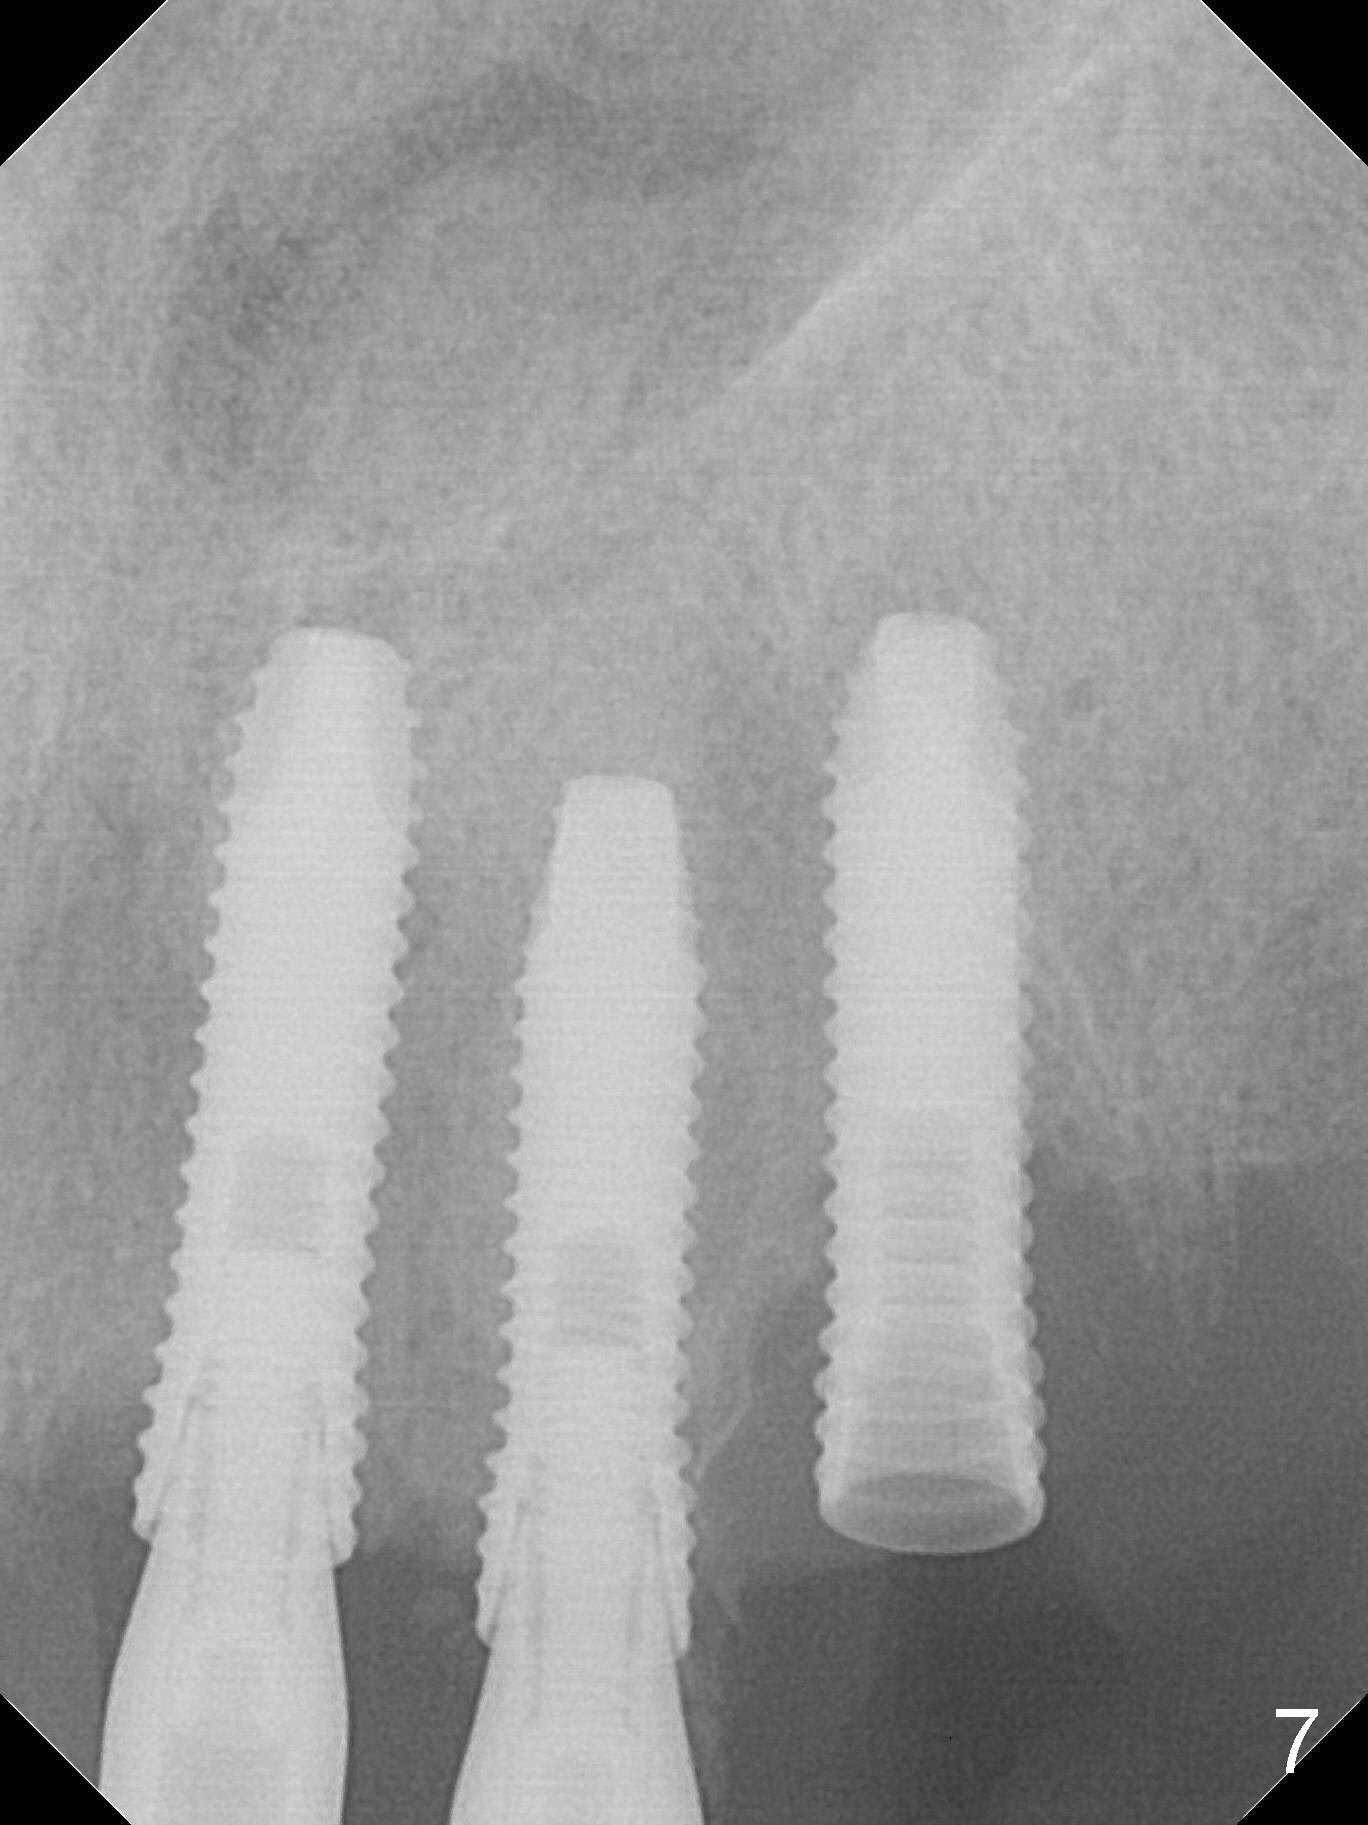

After use of 3 mm drill, the implant is reinserted at #11 with ideal trajectory (Fig.7). After further seating of the implant at #11, graft is placed in the remaining sockets of #9-11 (Fig.8 *; later more graft is placed mesial to #11 implant (^)). There appears no thread exposure 7 months postop (Fig.15,16).